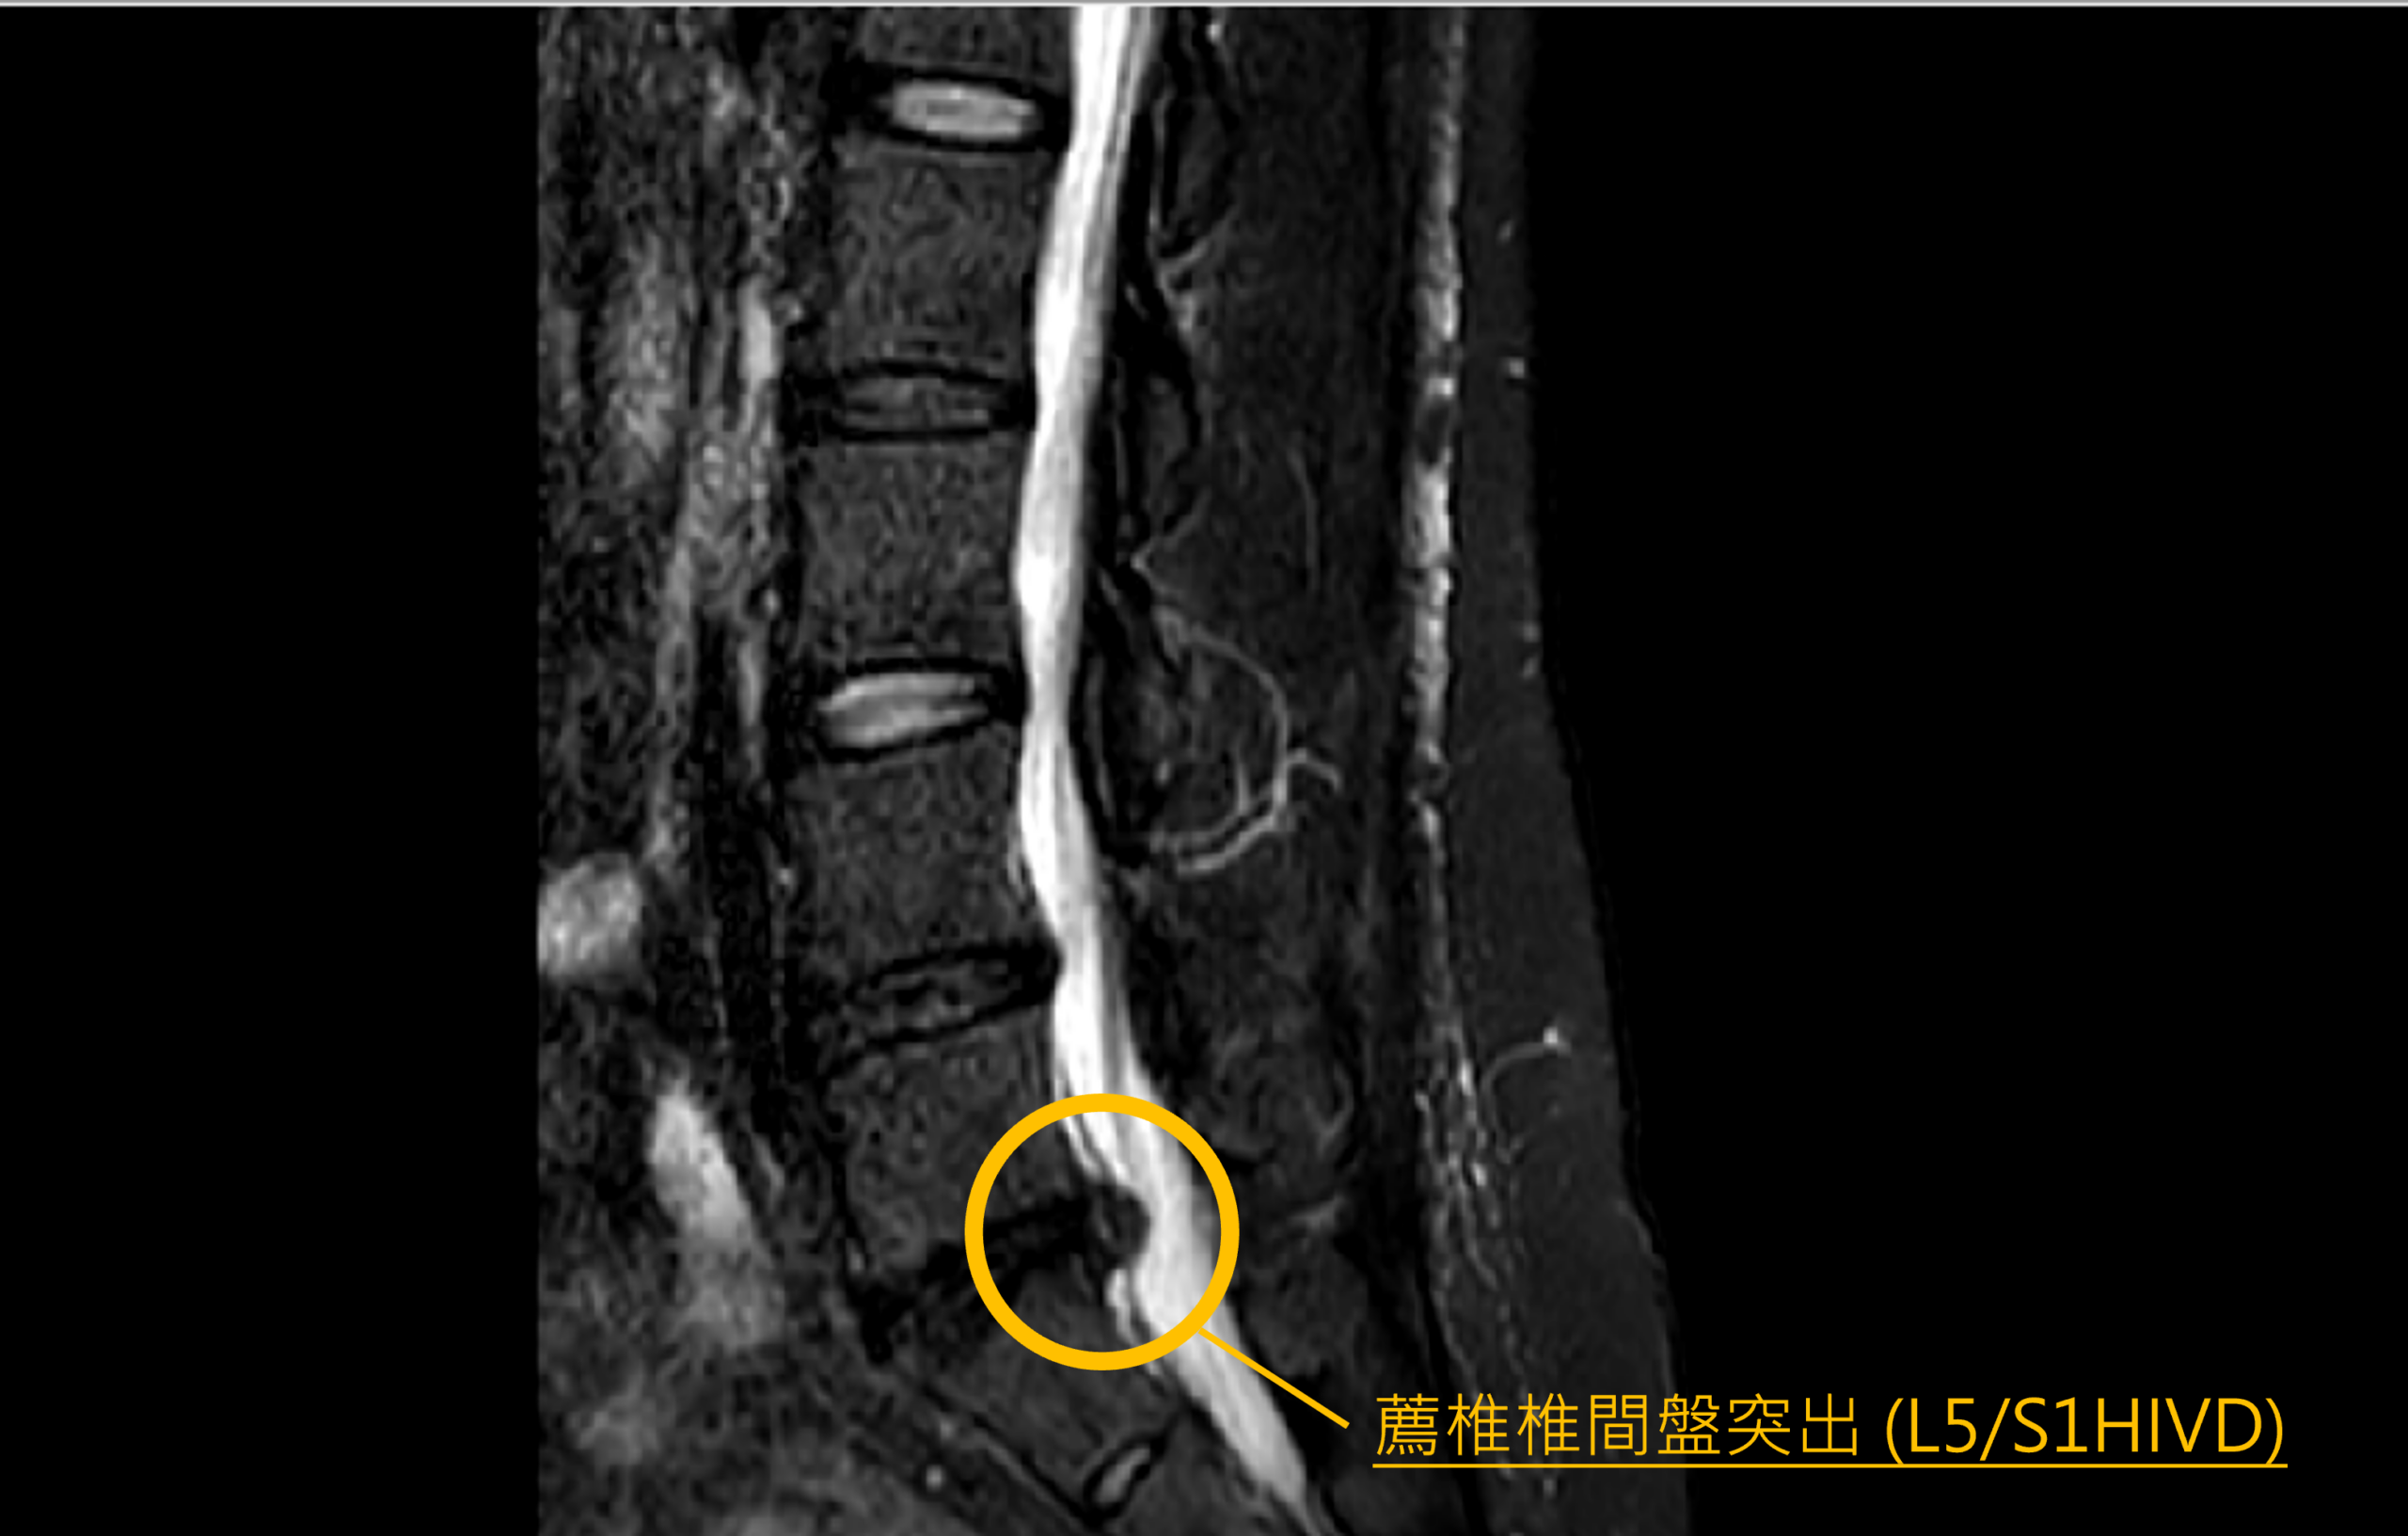

一個看似平常的家務動作,竟可能引發嚴重脊椎問題。日前一名50歲女性在家整理床鋪時,用力甩動棉被後,突然出現劇烈下背痛,並伴隨雙腳麻木,疼痛程度甚至影響行走能力。症狀持續兩周期間,曾接受復健治療但未見改善,最終前往衛生福利部桃園醫院脊椎專科門診就醫。經醫師安排核磁共振檢查後,確認患者為第五腰椎與第一薦椎間椎間盤突出,突出的椎間盤壓迫神經,導致下背痛與下肢麻木。醫療團隊評估後,為其安排單孔脊椎內視鏡椎間盤切除術微創手術,手術順利完成。患者術後第一天即可下床活動並開始復健,症狀明顯改善,第三天即順利出院返家,恢復日常生活。